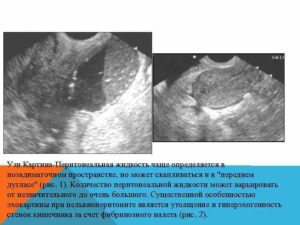

«Дугласово» пространство (карман, углубление) – анатомическая структура, которая характеризует углубление в малом тазу между задней стенкой матки и прямой кишкой у женщин. Его стенки покрыты брюшиной, которая в норме или в ответ на повреждающие факторы может продуцировать определенное количество жидкости.

На УЗИ жидкость за маткой определяется на анэхогенное (черное) включение неправильной формы в малом тазу без кровеносных сосудов. Достоверно определить объем крайне сложно, поскольку «Дугласов» карман не имеет постоянной или правильной формы, а его содержимое постоянно перемещается.

Осмотр анатомического углубления перед прямой кишкой осуществляется при продольном сканировании, когда полностью выведено тело и шейка матки.

Врач может косвенно определить уровень жидкости или объем.

В последнем случае необходимо использовать две проекции, чтобы получить три взаимно перпендикулярных размера, произведение которых потом следует умножить на специальный коэффициент – 0,523.